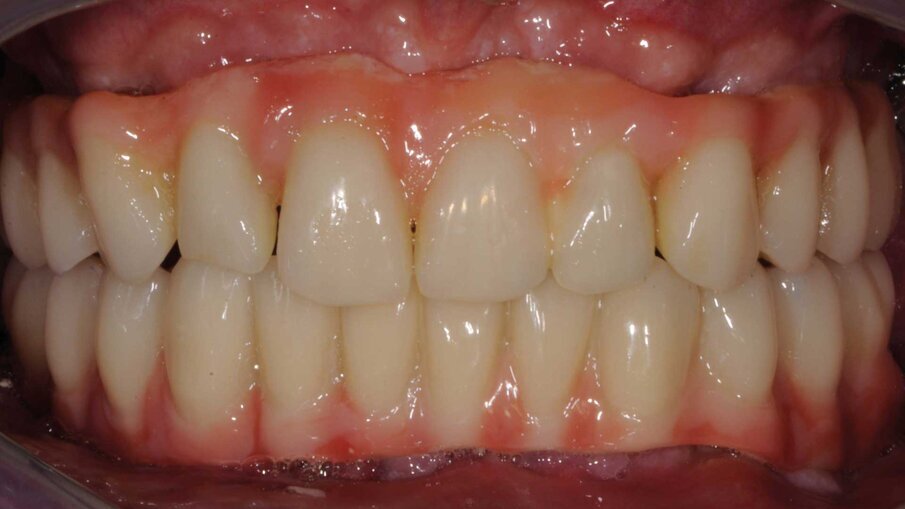

Dopo due giorni il paziente tornò in studio e le protesi Toronto provvisorie furono avvitate con semplicità, fu controllata l’occlusione, i fori di accesso delle viti furono sigillati con teflon e al di sopra fu applicato un composito Flowable. Il paziente fu dimesso e fu programmato un appuntamento di controllo a due settimane. Le suture furono rimosse prima della consegna del provvisorio e non si verificò né sanguinolento né apertura dei lembi grazie alle membrane di emocomponenti applicate attorno agli impianti che consentirono una rapida guarigione dei tessuti molli (Figg. 12, 13).

Molti pazienti si presentano nei nostri uffici con dentature molto compromesse. La maggior parte rifiuta l’idea di venire riabilitato tramite protesi totali rimovibili e apprezzano la proposta di una protesi tipo Toronto con carico immediato. Con questo case-report si vuole mostrare come sia possibile il carico immediato anche con impianti extra-corti che, oltre ad avere il vantaggio di una chirurgia mininvasiva, possono essere inseriti nei mascellari posteriori con carenza di osso evitando l’utilizzo di cantilever estesi che possono presentare alti stress attorno al collo degli impianti ed essere quindi un fattore di rischio.